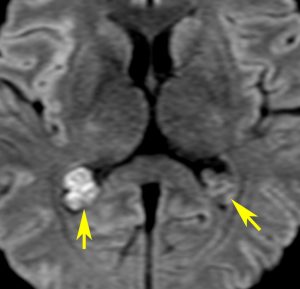

脳ドックなどでたくさん発見されるものです。両側に見られることが多いです。この患者さんは右側脳室の脈絡叢乳頭腫と診断されて来院されました。でも両側脳室三角部の脈絡叢のう胞です。右はガドリニウム増強ですが造影されません。これは経過観察の必要もなく放置してよいものです。